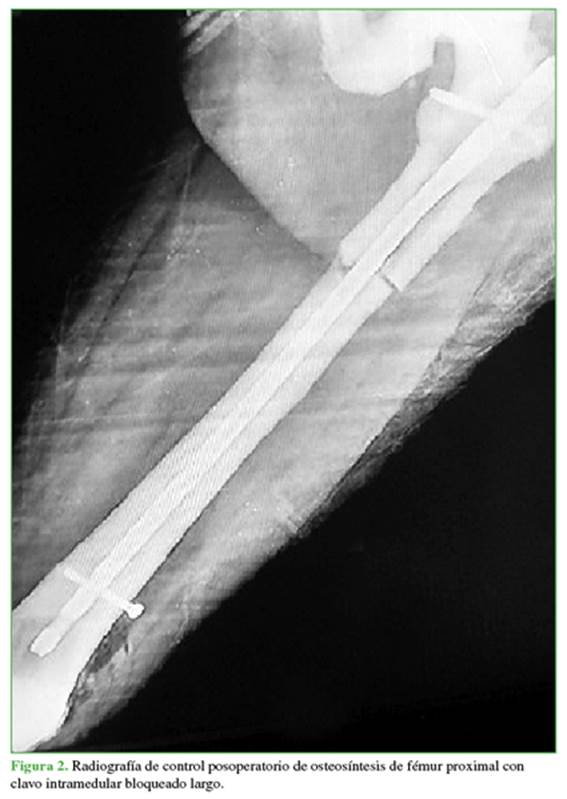

Mujer de 63 años, residente en la ciudad de Medellín, Colombia. Se trataba de una trabajadora independiente con diagnóstico previo de enfermedad de Paget de presentación poliostótica e historia familiar de enfermedad de Paget, diagnosticada de forma incidental por los hallazgos radiológicos y el antecedente familiar. En 2015, la paciente sufre una caída desde su propia altura y se comprueba fractura subtrocantérica de cadera izquierda, a la cual se le dio manejo quirúrgico en otra institución. Se considera que la fractura se presentó en hueso previamente patológico y comprometido por la enfermedad de Paget (Figuras 1 y 2).